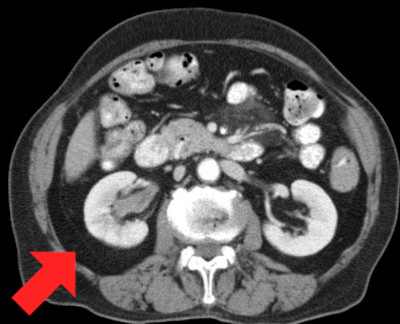

2)CT検査

CTでは、腫瘍の広がりのみでなく、リンパ節や他臓器への転移の検索にも有用です。造影剤(静脈内注射)を使用することでより詳細な情報が得られます。エコーと違い放射線の被爆の問題がありますが、通常の検査で心配することはありません。